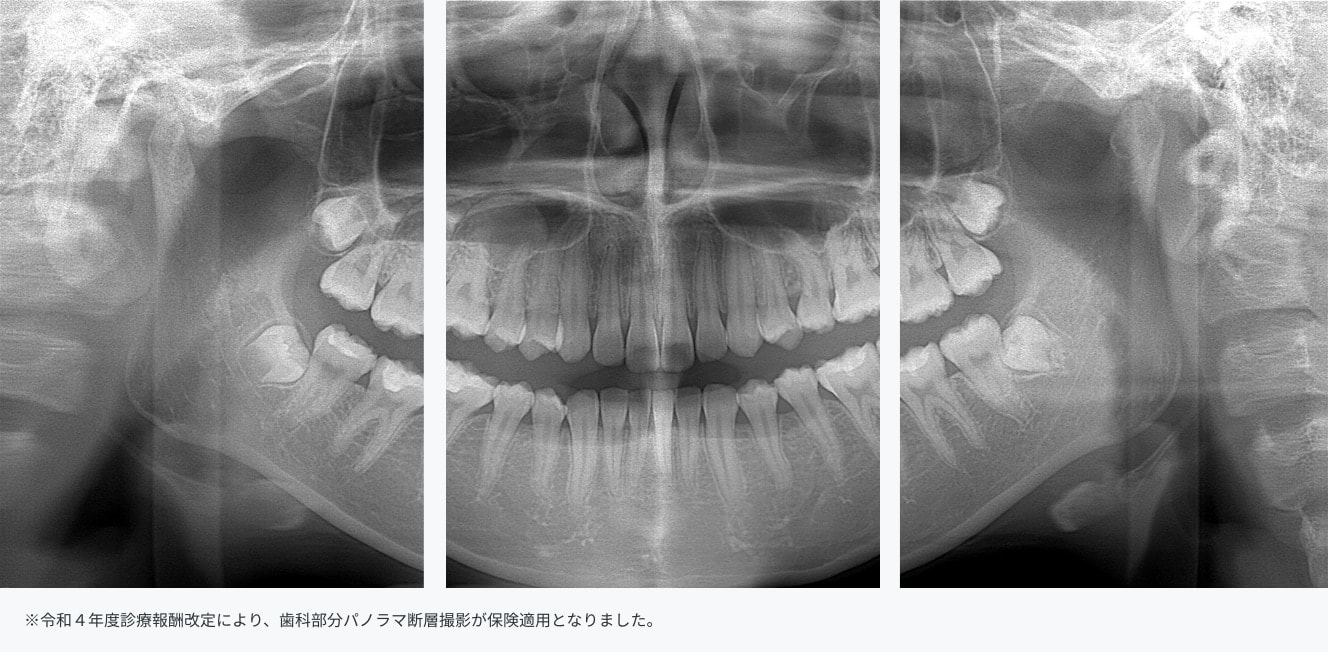

部分パノラマ撮影

撮影エリアを限定する部分パノラマ撮影が可能です。

嘔吐反射等でデンタル撮影等が困難な場合に、代替撮影法として活用いただけます。